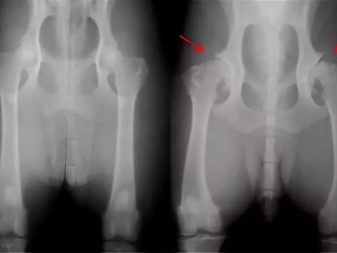

1. Hip dysplasia. In order for the risk of such a disease to be minimal, it is worth not physically loading the puppy at a young age. If the baby staggers, limps and at the same time remains in a sluggish state, then this may be a sign of joint dysplasia.If the diagnosis is confirmed, then the veterinarian should prescribe a drug treatment or surgery.

Hip dysplasia